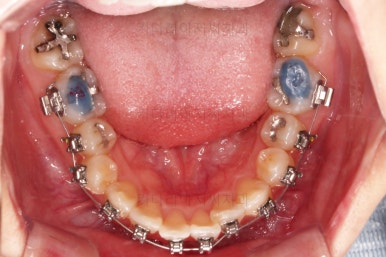

장치를 구성합니다.

이번 환자분은 윗니는 세라믹, 아랫니는 메탈 장치를 선택하셨는데요.

둘 다 물론 자가결찰 장치였고요.

동일한 제품의 장치이므로 혼용해서 쓰는게 가능합니다.

많이 보이는 부분은 세라믹, 잘 안보인다고 여겨지시는 부분은 메탈로 선택하면서 치료비 측면도 함께 고려한거죠.

장치 부착 직후의 모습인데요.